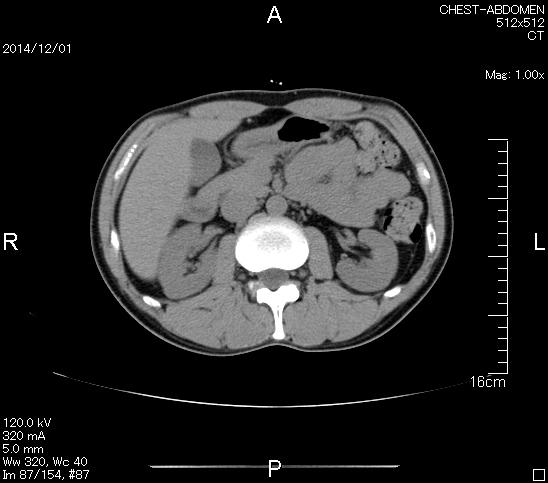

マーカー、CT画像、問題なし!!

今回も血液検査結果は正常値のパレード!

野菜中心の健康的な食事のおかげである。

Thank Youヨメ!!